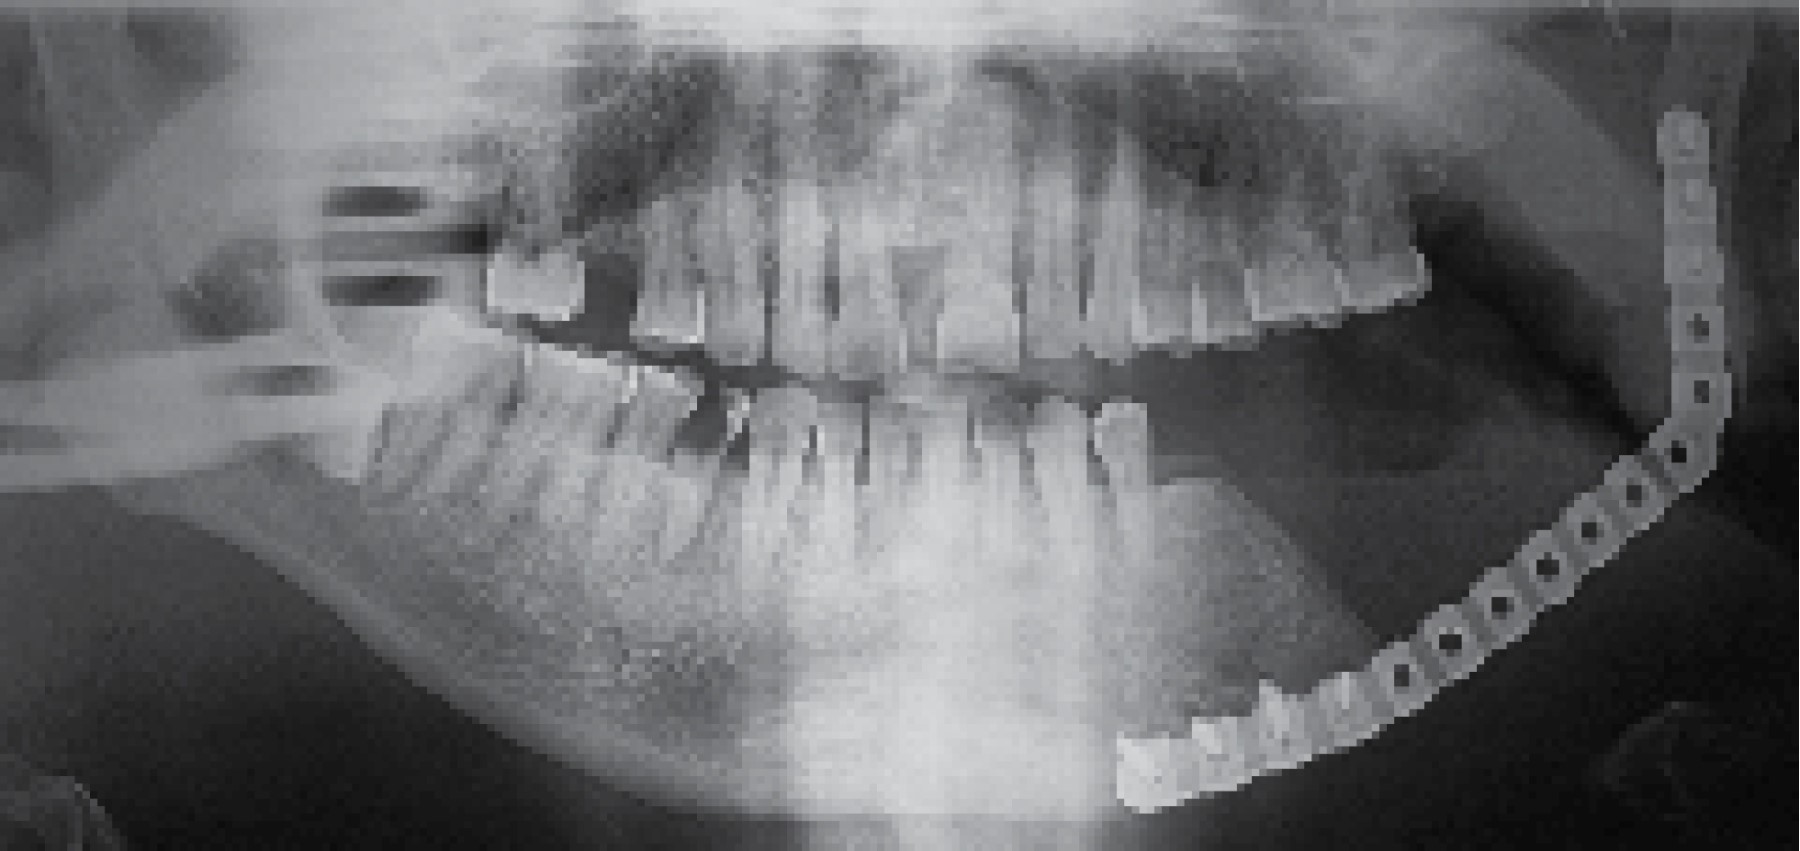

En enero de 2014 un paciente de 50 años de edad concurre al Servicio de Cirugía Maxilofacial del Hospital Zonal General de Agudos Manuel Belgrano presentando asimetría facial a causa de aumento de volumen en región geniana del lado izquierdo (Figura 1) con un estudio anatomopatológico con resultado de ameloblastoma multiquístico folicular en maxilar inferior. Como antecedente médico relevante el paciente padece diabetes tipo II. Se hicieron los estudios por imágenes de rutina (Figura 2) y en mayo de 2014, luego de firmar el consentimiento informado, se le realizó la resección segmentaria mandibular con un margen de seguridad de 1.5 cm, el cual permitió conservar el cóndilo mandibular, y se efectuó la reconstrucción inmediata con una placa de reconstrucción TMS 2.4 (WL, BIOMET) (Figura 3).

A los 30 días postoperatorios el paciente evolucionó con una fístula orocutánea con secreción purulenta (Figura 4). En conjunto con el servicio de infectología y luego de no haber una respuesta favorable al tratamiento no invasivo se decidió el retiro de la placa de osteosíntesis y cóndilo mandibular.

En agosto de 2015 se planificó la reconstrucción simultánea del componente mandibular y articular (Figura 5). A partir de este diseño se confeccionó una prótesis aloplástica personalizada Lorenz-Biomet (Biomet Microfixation, Jacksonville, FL, USA).

Figura 3

Figura 4